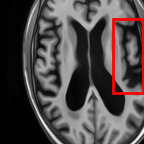

Sparsity LI 2D CNN 3D CNN Ours GT

8 Refer to caption (k) 0.5139/0.7240 Refer to caption (l) 0.6619/0.8224 Refer to caption (m) 0.6878/0.8584 Refer to caption (n) 0.7798/0.8853 Refer to caption (o) GM/WM

Refer to caption (p) 0.5910/0.6947 Refer to caption (q) 0.6516/0.8021 Refer to caption (r) 0.6507/0.8186 Refer to caption (s) 0.7471/0.8540 Refer to caption (t) GM/WM

Figure 6: Visual comparison of gray matter (Green)/white matter (Blue) segmentation over different methods, with respective DICE scores listed under the images.

In Fig. 6, we demonstrate the advantage of the proposed method in brain matter segmentation. It is clear that although 2D and 3D CNN generates visually plausible interpolation as presented in Fig. 5, the brain matters are easily misclassified due to incorrect anatomical structures and blurred details.